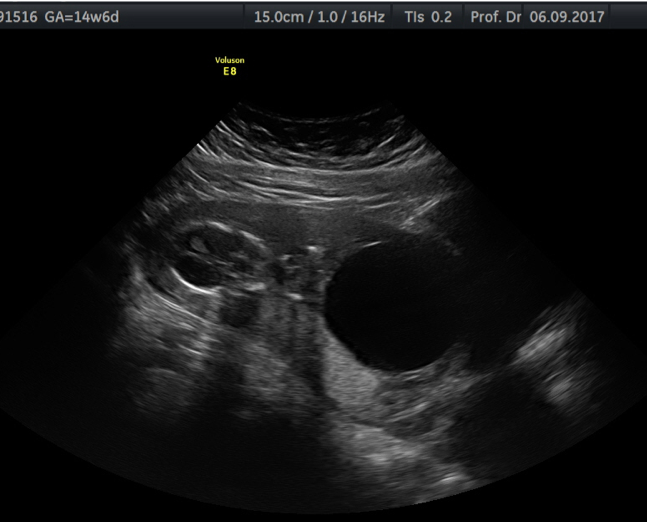

Correct! The sonogram shows a foetus with an anhydramnion and a huge bladder which shows a lower urinary tract obstruction (LUTO). The aetiology of LUTO is heterogeneous. The most common entities are isolated posterior urethral valves or urethral atresia in male foetuses. In female foetuses, LUTO is frequently a part of complex malformations. The natural history of LUTO is characterised by high morbidity and mortality due to the development of severe pulmonary hypoplasia caused by oligo- or anhydramnios affecting the cannalicular phase (16–24 weeks of gestation) of pulmonary development.The degree of renal damage is variable and ranges from mild renal impairment in infancy to end-stage renal insufficiency, necessitating dialysis and transplantation.